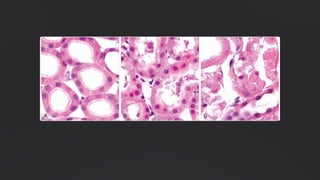

Necrose Caseosa

Típica de infecção tuberculosa, com

aparência friável branco-amarelada

("semelhante a queijo").

Microscopicamente, exibe células

rompidas com aparência granular

amorfa rósea. A arquitetura do tecido é

completamente destruída,

frequentemente circundada por

macrófagos e células inflamatórias.